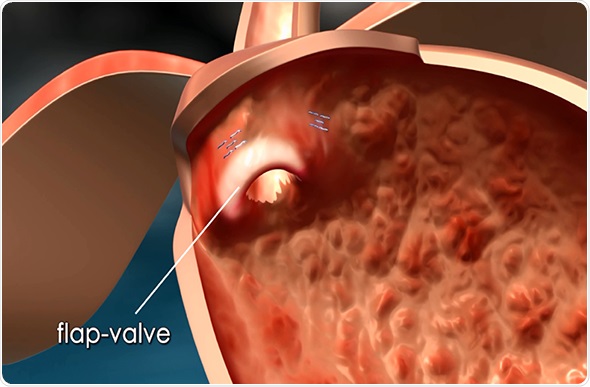

The MUSE endostapler is progressed into the stomach through an overtube and retroflexed under direct video guidance. After identifying an ideal stapling location, the stapler is gently pulled back to place the staple cartridge in the lower esophagus approximately 3cm above the gastroesophageal junction. The procedure typically delivers about five staples to effectively reinforce the LES.

The device’s video camera offers direct visualization during insertion and staple site selection, and ultrasound to determine when a proper stapling gap is achieved.